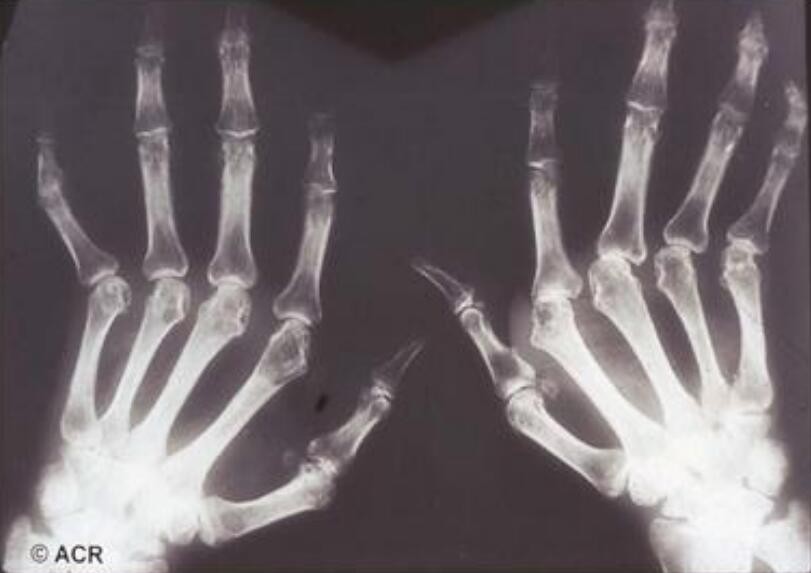

風濕吃蜂王漿還是有一定好處的,風濕大多有關節病變和癥狀,會有紅腫、疼痛以及功能受損等多方面炎癥的表現。蜂王漿中的王漿酸有很強的殺菌消炎的作用,可以清除身體內的一些細菌,對于炎癥和紅腫都有一定的緩解作用。